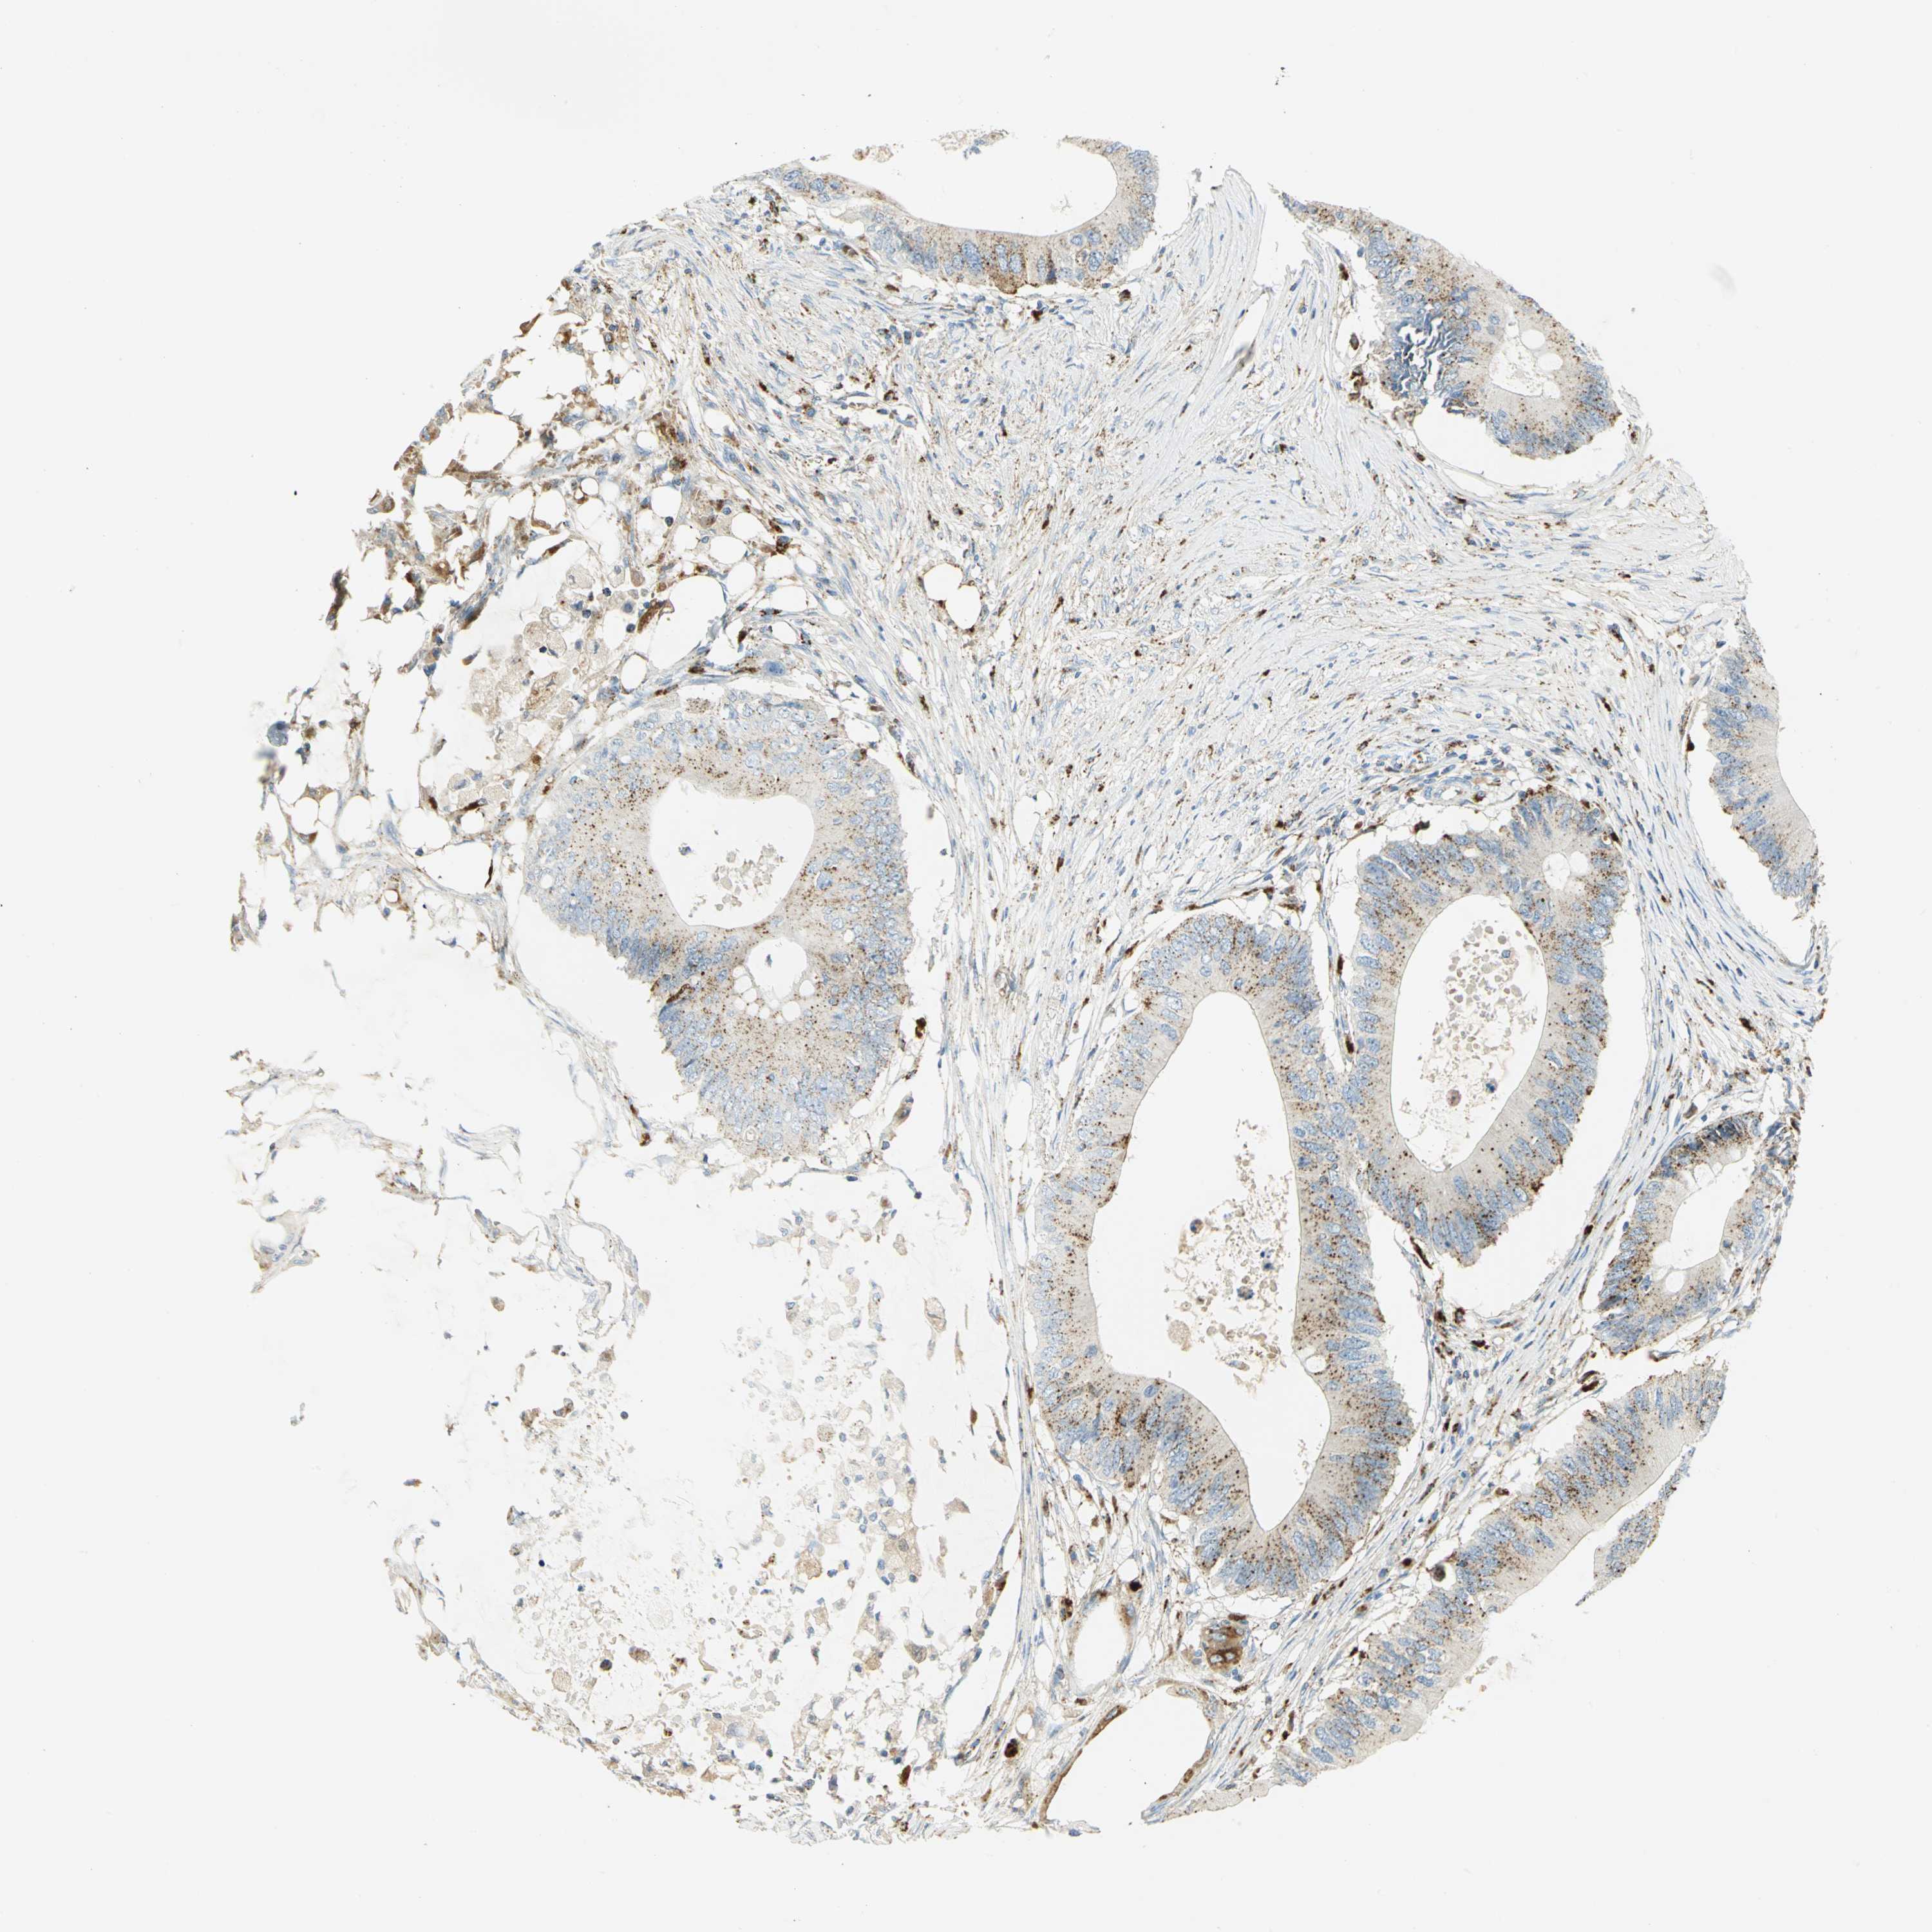

CANCER COLORECTAL CANCER Show tissue menu

Colorectal cancer

Human cancer

Colon adenocarcinoma